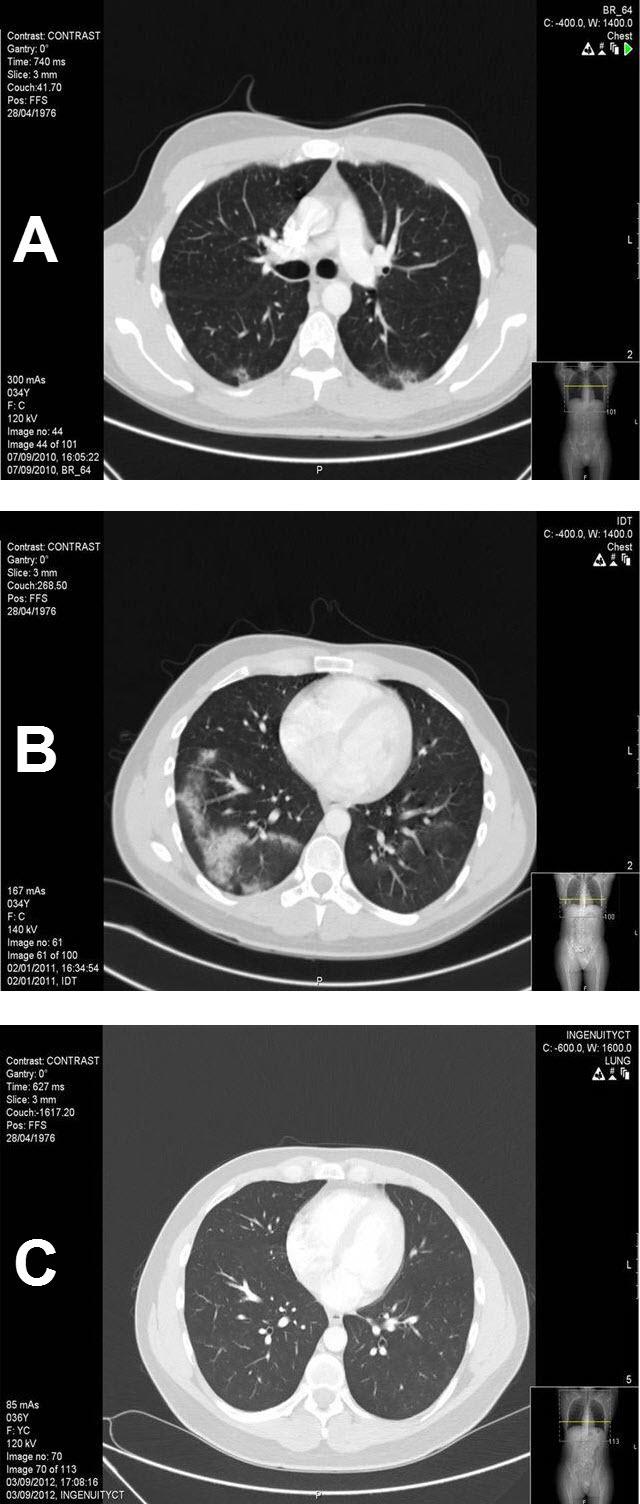

Before chemotherapy, meticulous staging was done, including tumor markers (B-human chorionic gonadotropin (B-HCG), alpha-fetoprotein (AFP), and lactic dehydrogenase (LDH)), and abdominal and pelvic computerized tomography (CT) scans were carried out.

All 26 treated patients achieved complete remission, clinically and symptomatically, with normalization of their CT scans. At a median follow-up of 120 months (range, 24-268 months) all patients are alive, without evidence of recurrent disease. One patient whose disease recurred twice achieved a third complete remission following salvage treatment with high-dose chemotherapy and autologous peripheral stem cell transplantation. Another patient, who preferred surveillance, relapsed abdominally after 9 months but achieved long-standing complete remission with cisplatin-based chemotherapy. Both these patients are alive with no evidence of disease. Three patients recovered uneventfully from bleomycin-induced pneumonitis.

化疗前进行了细致的分期,包括肿瘤标志物(β - 人绒毛膜促性腺激素(β - HCG)、甲胎蛋白(AFP)和乳酸脱氢酶(LDH)),并进行了腹部和盆腔计算机断层扫描(CT)。

所有26例接受治疗的患者在临床和症状上均实现了完全缓解,CT扫描结果正常。中位随访120个月(范围为24 - 268个月)时,所有患者均存活且无疾病复发迹象。一名疾病复发两次的患者在接受大剂量化疗和自体外周干细胞移植的挽救治疗后实现了第三次完全缓解。另一名选择观察的患者在9个月后腹部复发,但通过基于顺铂的化疗实现了长期完全缓解。这两名患者均存活且无疾病迹象。3例患者从博来霉素引起的肺炎中顺利康复。